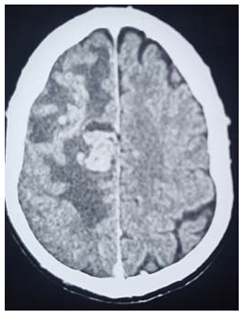

# Case 19:

This 37 years female, employer, has history of recurrence uterine fibroid, presented to neurosurgery emergency unit, with history of rabidly progressing focal convulsions and Lt side weakness over few weeks before her presentation. On examination, there is Lt side weakness with power grade II

Operation: Before surgery, we speak to the patient and her family and explained the outcome of surgery, Rt parietal craniotomy was done, the tumor sub cortical located, capsulated with massive brain edema surrounding, macroscopic total excision was done.

After recovering, she developed focal fits ipsilateral to the lesion, and thus IV diazepam was given to abort the fit.

Patient was taken to the ICU

She showed mild improvement in the motor power

Histopathology

Metastatic carcinoma, ultimately patient was planned to be evaluated at Merowe town isotope center.